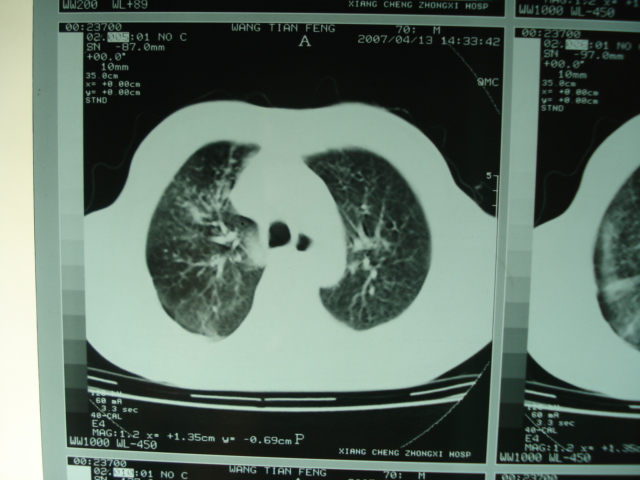

以下是引用狙击手在2007-4-18 20:17:00的发言:[br]原:2007/1/22号ct片:右肺上叶可见片状、云雾状高密度影,右肺上叶后段可见三角形高密度影,尖端指向肺门,右肺上叶后段支气管壁不规则增厚,管腔不规则增厚,纵隔未见肿大淋巴结.[br] 今ct:右肺上叶片状影增大,右肺上叶后段不张及右肺上叶后段支气管壁不规则增厚未见变化,右肺下叶背段支气管壁不规则增厚.[br] 如果考虑肺结核,但从临床证据看竟然没有一项支持肺结核,不知患者是否已经过正规抗结核治疗。没有的话,3个月了前后片看起来变化不大,似乎有不太符合肿瘤征象,不知患者是否抗炎治疗过,下叶支气管增粗还是要高度警惕,同意楼主意见,将常规病理,生化检查再做一遍。[br]

以下是引用狙击手在2007-4-18 20:17:00的发言:[br]原:2007/1/22号ct片:右肺上叶可见片状、云雾状高密度影,右肺上叶后段可见三角形高密度影,尖端指向肺门,右肺上叶后段支气管壁不规则增厚,管腔不规则增厚,纵隔未见肿大淋巴结.[br] 今ct:右肺上叶片状影增大,右肺上叶后段不张及右肺上叶后段支气管壁不规则增厚未见变化,右肺下叶背段支气管壁不规则增厚.[br] 如果考虑肺结核,但从临床证据看竟然没有一项支持肺结核,不知患者是否已经过正规抗结核治疗。没有的话,3个月了前后片看起来变化不大,似乎有不太符合肿瘤征象,不知患者是否抗炎治疗过,下叶支气管增粗还是要高度警惕,同意楼主意见,将常规病理,生化检查在做一遍。[br]